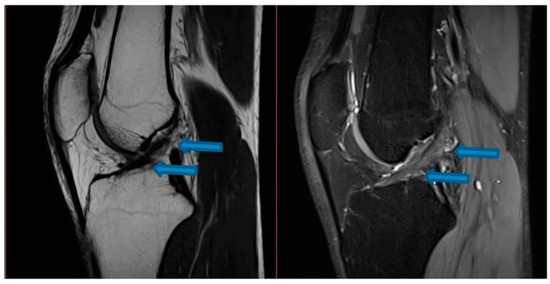

| 9 November 2020 | MRI scans demonstrating signs of partial ACL healing |

| 14 August 2021 | MRI scans demonstrating signs of complete ACL healing |

| 24 December 2021 | MRI scans confirming signs of complete ACL, MCL and medial meniscus healing |